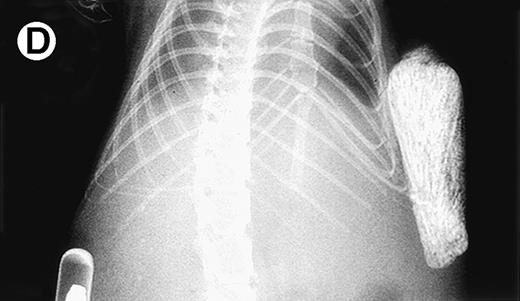

Growth of myeloma blood cells from patient no. 10 in SCID-hu host. SCID-hu host was inoculated with blood cells (containing 0.1% plasma cells) and with PC-depleted blood cells. (A) Human Ig levels. (•) Blood cells; (○) PC-depleted blood cells; (▪) host inoculated with bone marrow cells containing 11% myeloma plasma cells. (B) Flow cytometry dot plot of CD38CD45 profile of the blood cells. The sort window excluding CD45− and CD45+plasma cells is shown. (C and D) X-radiograms of host injected with blood cells (C) and with PC-depleted blood cells (D). Note severe decalcification of myelomatous human bone in (C).